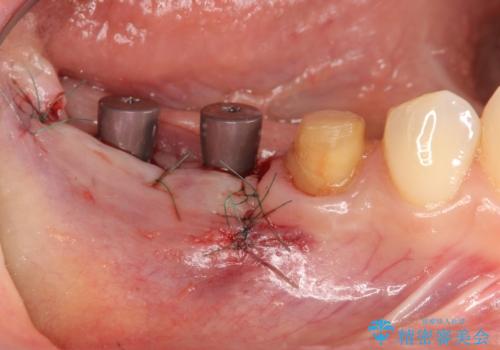

インプラント治療による咬合機能回復

- 失ってしまった奥歯の咬合機能の回復を求めて来院されました。

骨の幅が十分にないのでインプラント治療に伴い、人工骨の造成を同時に計画します。

長年安心してしっかりと噛んでいただけるよう今回は骨を増成する治療計画としました。